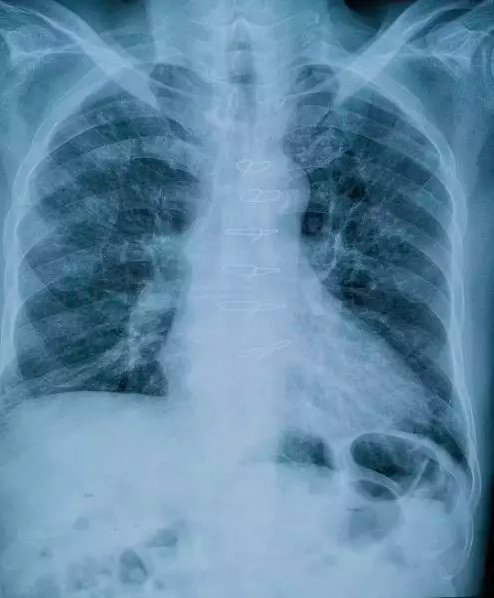

近期治疗后的肺部影像

讲完课后,他马上赶回父亲身边。在北京大学人民医院重症医学科刘方教授的帮助下,他先后找到协和医院感染内科马小军教授、空军总医院副院长张波教授、北京大学肿瘤医院郭军教授等业界“大拿”求救。专家推断,前面血氧下降,主要是肿瘤浸润的出血间质水肿造成的呼吸衰竭。最终给出了靶向加上PD1联合治疗的方案,抗生素逐渐减下来。

情况终于得到控制,在春节到来时,老先生转危为安!100天的煎熬总算没有白费!